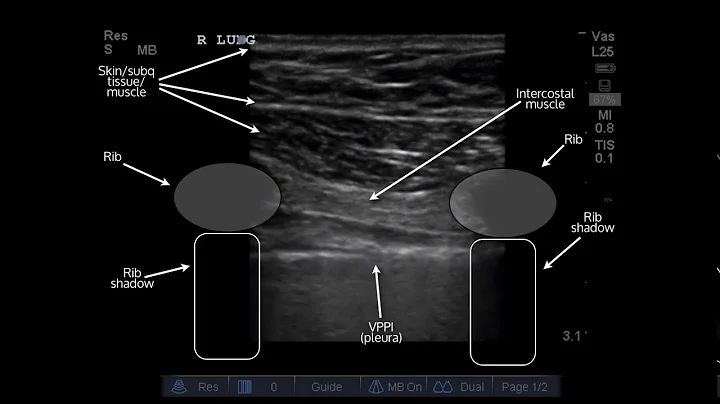

Lung Ultrasound Explained (point Of Care, Bedside, Clinical)

Lung Ultrasound for Point of Care Clinicians clearly explained bedside by Joshua Jacquet, MD. See the rest of the videos in this ...